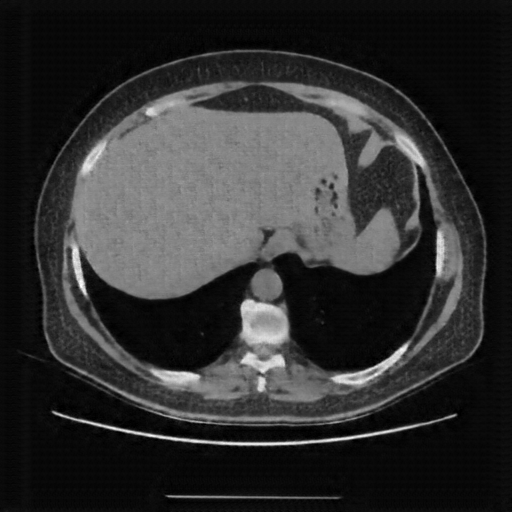

Generated VENOUS CT scan (A→B translation)

Lung window (WL -600, WW 1500 β†’ Low βˆ’1350, High +150)

Actual HU range: [-1119.6, 150.0]